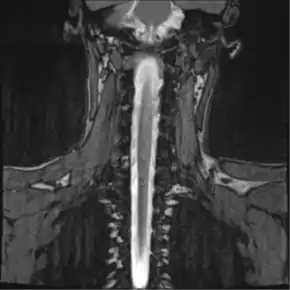

![]() Thoracic MR Myelogram |

Magnetic resonance myelography (MR myelography or MRI myelography) is a noninvasive medical imaging technique that can provide anatomic information about the subarachnoid space. It a is type of MRI examination that uses a contrast medium and magnetic resonance imaging scanner to detect pathology of the spinal cord, including the location of a spinal cord injury, cysts, tumors and other abnormalities. The procedure involved the injection of a gadolinium based contrast media into the cervical or lumbar spine, followed by the MRI scan.[1][2]